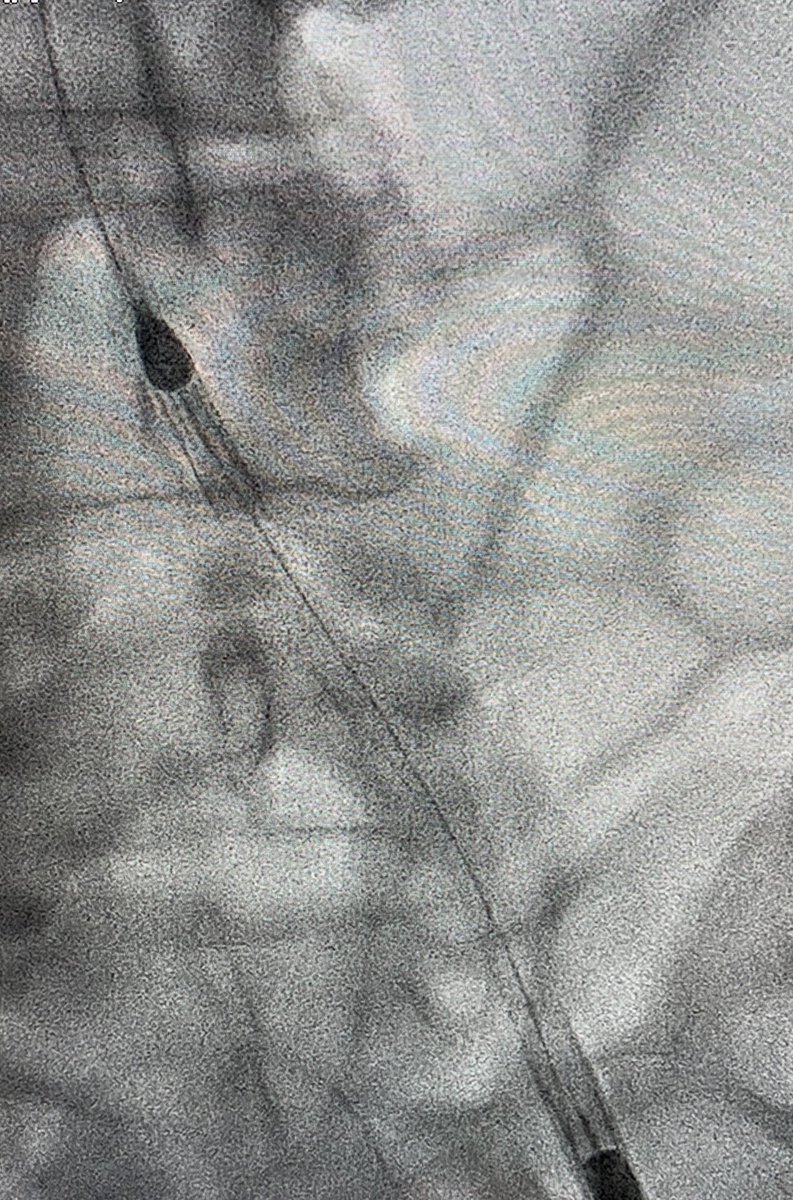

3/7 Impella observed going in. Take a moment to remove slack, achieve stable device position. Always place Swan with Impella in Shock...

4/7 Quick single-access (a la @jason_wollmuth et al) run-off angiogram at the very end confirming distal flow before removing peel-away sheath (or can perform via Radial access) to assess need for antegrade perfusion catheter...